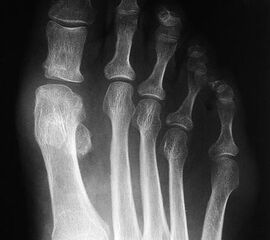

• Röntgenaufnahme des Vorfußes im Stand in 2 Ebenen (dorsoplantar, mediolateral)

• Beurteilung der degenerativen Veränderungen am Röntgenbild nach der Einteilung von Hattrup und Johnson (1988) 11.

• Beurteilung des Intermetatarsalwinkels (Intermetatarsal angle - IMA), des Hallux valgus Winkels (Hallux valgus angle - HVA) und des distalen Metatarsalegelenkflächenwinkels (Distal metatarsal articular angle - DMAA).